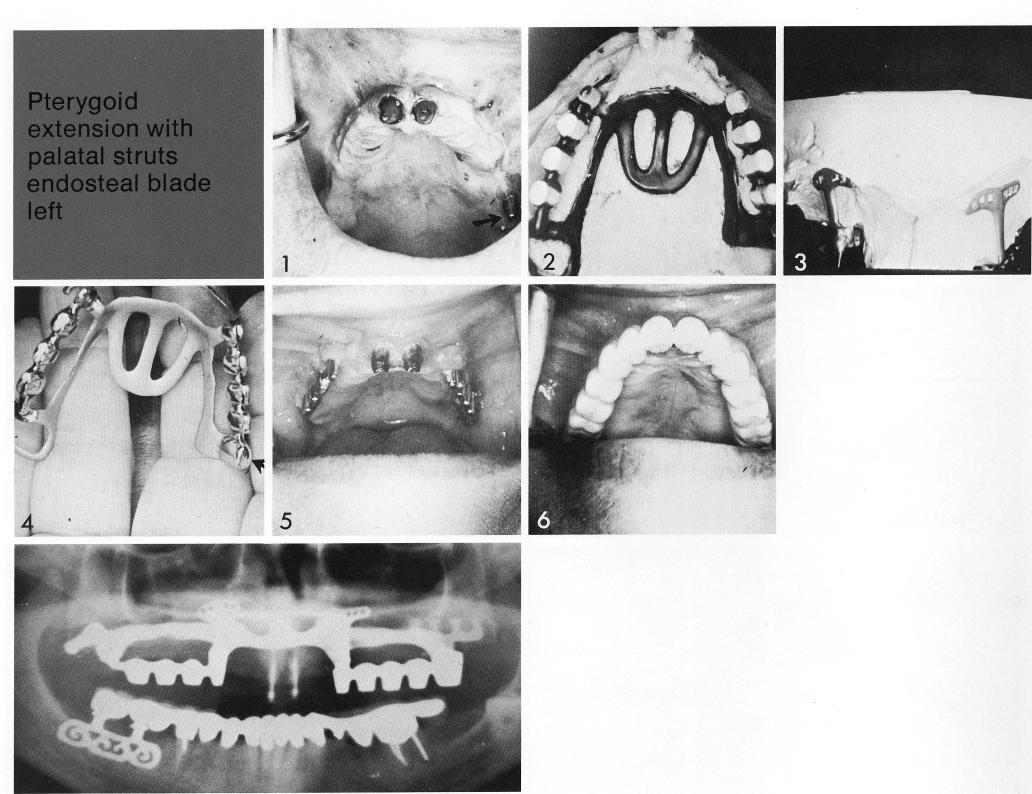

Pterygoid extension with palatal struts

endosteal blade

left

In this unusual case, a posterior bladevent extends into a sturdy tuberosity to provide—together with two anterior teeth—auxiliary endosteal support (1) for a modified pterygoid extension implant. The implant extends around the entire arch on the hard palate (2), with labial extensions flanking the teeth (3). The posterior anchor on the right side is a pterygoid extension, the other a coping for the bladevent (4, arrow). An impression is taken over the healed tissues (5) for the final restoration (6).

1 Posterior maxillary bladevent implant extends into a sturdy tuberosity